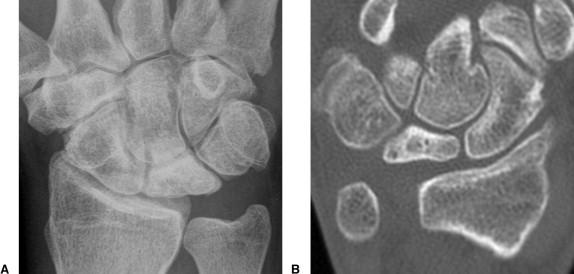

육체노동을 많이하는 남자에서 생기는 질환입니다. ulnar impaction syndrome 과는 반대로 ulna variance가 음성인 경우가 많으며

정맥 관류 차단에 의한 골내압력증가로 인하여 괴사가 진행된다고 추측하고 있는 질병입니다.

증상으로는 파악력이 감소되며 수근 관절 굴곡 제한이 많이 있습니다.

치료가 단계마다 다르기 때문에 분류가 중요합니다.

Lunate 의 sclerosis가 발견되면 Stage II 이며 Joint leveling 이 핵심입니다. ulna 변위가 중립 혹은 양성인 경우에는 radial wedge osteotomy나 그 외의 치료를 시행해 볼 수 있습니다.